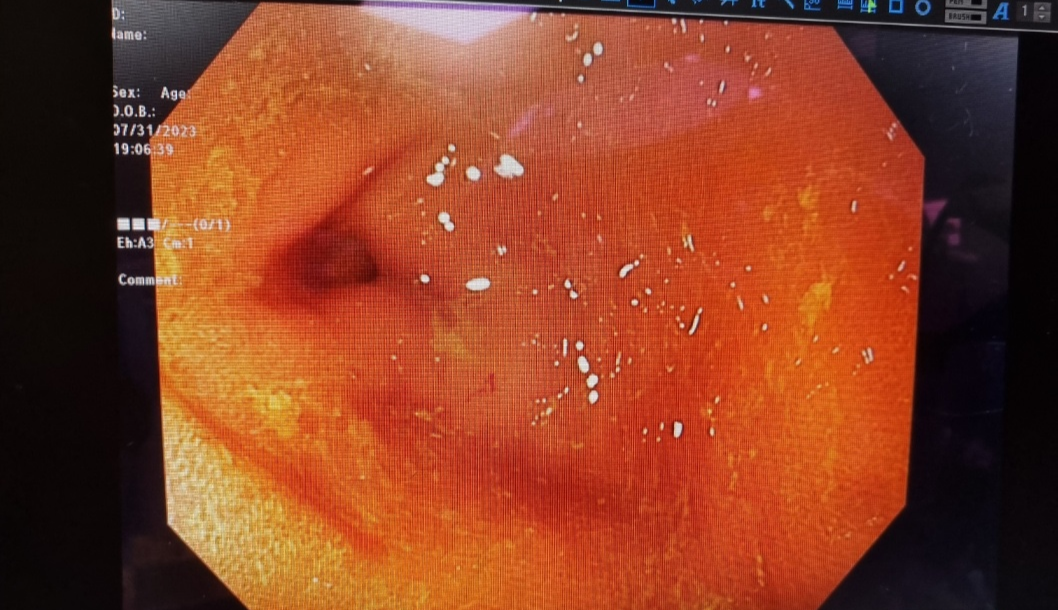

이렇게 병원을 바꿔가면서 6개월정도를 고생하다가 결국 2차 병원에서 CT와 대장내시경을 했습니다.

2차 병원은 분당리더스병원을 갔습니다. 일반적인 검사들 (피검사, x-ray, 초음파 등) 모두 정상으로 나왔습니다. 여기서도 출혈성 장염을 의심하고 새로운 약을 써본다고 하셨음. 하지만 약이 듣는가 싶더니 또 피똥을 심하게 싸기 시작. 이제는 거의 한 달째 다니고 있는데 마지막이라고 생각하고 CT와 대장내시경을 해보기로 했습니다.

이 두 검사를 하기위해서는 마취를 해야하는데 소형견이거나 나이가 많은 경우 마취 후 깨어나지 않을 수 있는 위험성이 어쩔수없이 있다고 해요. 아무튼 그렇게 동의서 작성후 검사가 들어갔고, 결과는 정말... 다행이면 다행이지만 아무 이상이 없었습니다.

위, 대장 전부 깔끔했지만 위벽과 대장벽이 굉장히 얇아져있어서 출혈이 있는 것 같다고 합니다. 위벽, 대장벽이 얇아지는 건 강아지의 나이 때문에 그런 경우가 많다고 해요. 위장보호하는 약과 위, 대장에 무리를 주지 않는 음식으로 바꿔 먹이면서 관리하고 있습니다.

위와 대장에 종양이나 다른 이상은 없었지만 위벽과 대장내벽이 얇아져 음식물이 지나가면서 위와 장에 출혈이 생겨서 변에 피가 묻어 나오는 거였다. 의사 선생님 말로는 나이가 들면서 위와 대장이 약해졌고 더 이상 약물치료나 다른 치료를 통해 할 수 있는 게 없다고 하셨다. (그전에 약물치료를 2주간 했었음)